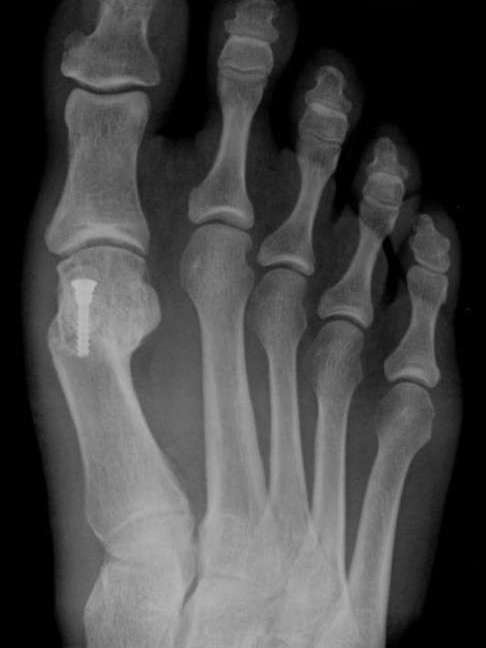

Halluks valgus cerrahisi uygulanmış hastanın röntgen filmi

Tüm ayak girişimlerinden sonra ayakta hafif de olsa ağrı, şişlik ve hareket kısıtlılığı gibi bazı yakınmaların kalacağı unutulmamalı, hiçbir ayak ameliyatı yalnızca estetik kaygılarla yapılmamalıdır. Yalnızca ağrılı bir halluks valgus için ameliyatı düşünmelidir.